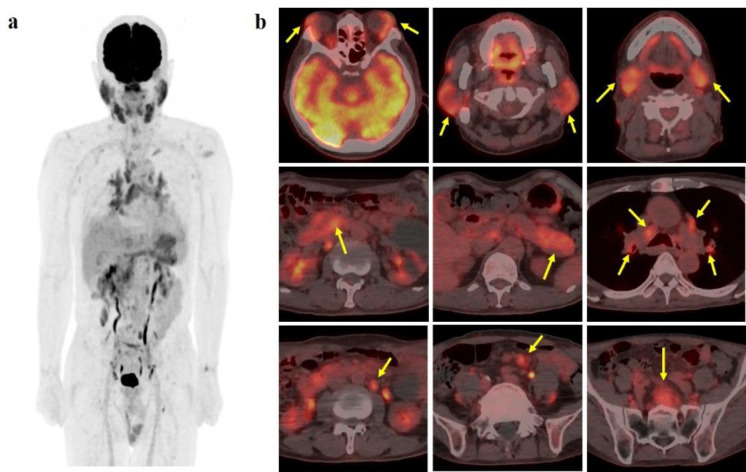

18F-FDG PET/CT is regarded as a modality utilized for the purpose of lesion localization, staging and assessment of treatment response in patients with lymphoma. However, it is difficult that we diagnose among multifocal lymphoma, IgG4-related disease (IgG4-RD), or a combination of both conditions when confronted with multiple sites of 18F-FDG uptake with heightened serum IgG4 levels. We present a case of a 72-year-old male who was suspected of Sjögren's syndrome based on symptoms of xerostomia accompanied by swelling of the bilateral upper eyelid and salivary glands. Following a diagnostic biopsy that revealed mucosa-associated lymphoid tissue (MALT) lymphoma as a possible finding, 18F-FDG PET/CT was conducted, which demonstrated multiple sites of 18F-FDG accumulation. While multifocal MALT lymphoma was initially suspected, the coexistence of IgG4-RD could not be definitively ruled out due to the elevated serum IgG4 levels. Subsequent histopathological and immunohistochemical examinations confirmed the diagnosis of IgG4-producing MALT lymphoma. After receiving systemic therapy with rituximab, the swelling of the bilateral upper eyelid and parotid glands resolved upon visual examination, and the serum IgG4 levels returned to within the normal range in a few months. No new lesions were detected during the subsequent follow-up examinations conducted over a period of 3 years.